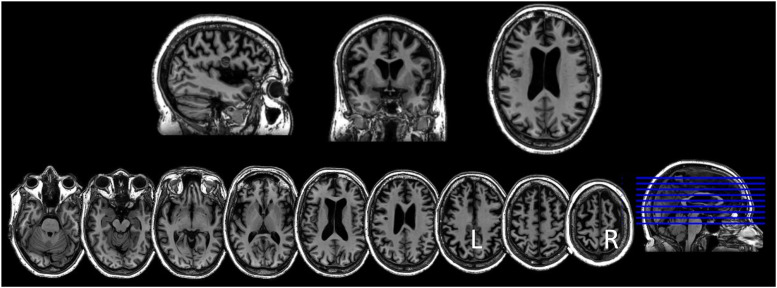

We present the case of a 62-year-old woman with probable behavioral variant of frontotemporal dementia (bvFTD) with cognitive/language deficits who demonstrated improved performance on cognitive/language testing and in functional tasks following long-term, home-based transcranial direct current stimulation (tDCS) coupled with computerized cognitive training (CCT). The patient underwent home-based tDCS (anode on the left prefrontal cortex and cathode on the right homologue) for 46 sessions over 10 weeks along with CCT. On post-treatment testing, the patient improved by 3 points on the Mini-Mental State Exam (MMSE) (23 to 26). She also showed improvement on several cognitive/language tasks, such as immediate recall of single words and word pairs, total accurate words in sentence repetition, delayed recall, semantic processing, and sentence level comprehension. There was no decline in several other cognitive and language tasks. Family members reported subjective improvements in expressiveness, communication, and interaction with others as well as increased attention to grooming and style which contrasted with her pre-treatment condition. This report suggests that home-based tDCS combined with CCT for an extended period may slow decline, and improve cognitive/language performance and everyday function in FTD.